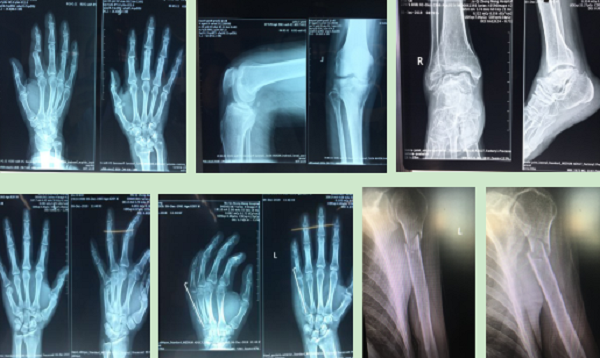

12月份门诊诊疗病例116人次,病种多为腰椎间盘突出症、腰椎管狭窄症、梨状肌紧张综合征、颈椎病、肘管综合征、胸腰椎小关节紊乱症、膝关节骨性关节炎、膝关节滑膜炎、肩关节周围炎、股骨头坏死、距骨坏死、指骨骨髓炎、丹毒、痛风性关节炎及桡骨远端骨折、肱骨骨折、股骨颈骨折、踝关节骨折、掌骨骨折、指骨骨折、跖骨骨折、趾骨骨折、肩关节脱位、指间关节半脱位等。

手法整复桡骨远端骨折、肱骨骨折、踝关节骨折、掌骨骨折、指骨骨折、跖骨骨折及肩关节脱位、桡骨小头半脱位等各类骨折脱位十余例,行小夹板固定及石膏托外固定十余例。

参与完成髋关节置换术、尺神经前置术、跟骨骨折钢板螺钉取出术、尺桡骨骨折钢板螺钉内固定取出术、掌骨骨折钢板螺钉取出术及清创缝合术等手术六例。